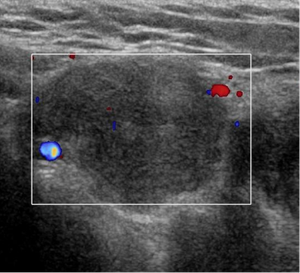

A 17-year-old male patient, no past medical history, presented with two-month history of left groin swelling with gradual increase in size and now pain.